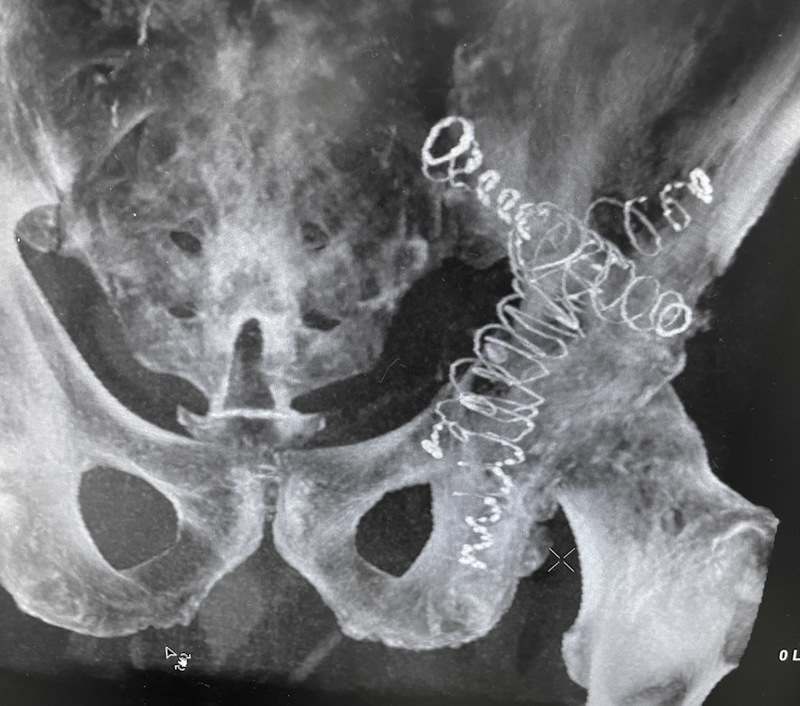

The 63-year-old patient presented with a pathologic acetabulum/hemi-pelvic fracture, and osteolysis with uncontained defect from metastatic lung cancer and additional co-morbidities. The patient has been treated with radiation for metastatic bone disease of the pelvis, and was bed ridden living in a skilled nursing facility due to severe pain and dysfunction resulting from his pathologic pelvis fractures. The patient was brought to surgery and IlluminOss implants were inserted percutaneously through the posterior column, anterior column and LC2 to provide fill and stability for the uncontained osteolytic defect. The implants were filled with a photodynamic liquid monomer and cured with visible blue light. At post-op day 1, the patient was weight bearing as tolerated using a walker. The patient was discharged back to the SNF on post operative day 1 and then from the SNF to home at 2 weeks post procedure. At 6 weeks follow up, patient uses the walker in the community and ambulates unassisted intermittently at home.